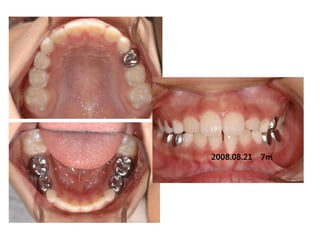

S.H. Jang

1999.10.14/M

C.C

• Max. protrusion

• Lower crowding

Dx

• Mouth breathing, retro-positioned tongue

Goal

• Lip seal(Adenoidectomy and Tonsilectomy)

• Establish tongue posture with T4K

2006.07.21

A &T 2008.01 Tr start

2007.11.21

2008.05.08 4m

2008.08.21   7m